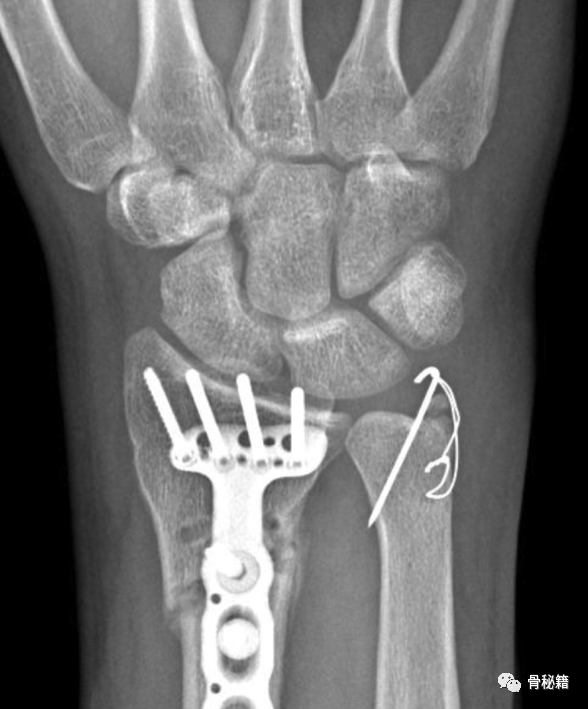

3 对于近端和比较复杂的骨折,建议采用钢板固定,这样可以带来相对较好的稳定性

最常用的是尺背侧入路

最后给大家提供一种可延伸的切口,作为复杂尺骨骨折的入路